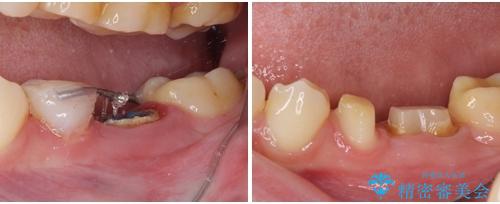

根歯の挺出(歯を引っ張り出す部分矯正)、歯周外科処置などを行った後、オールセラミッククラウンにて補綴することとしました。